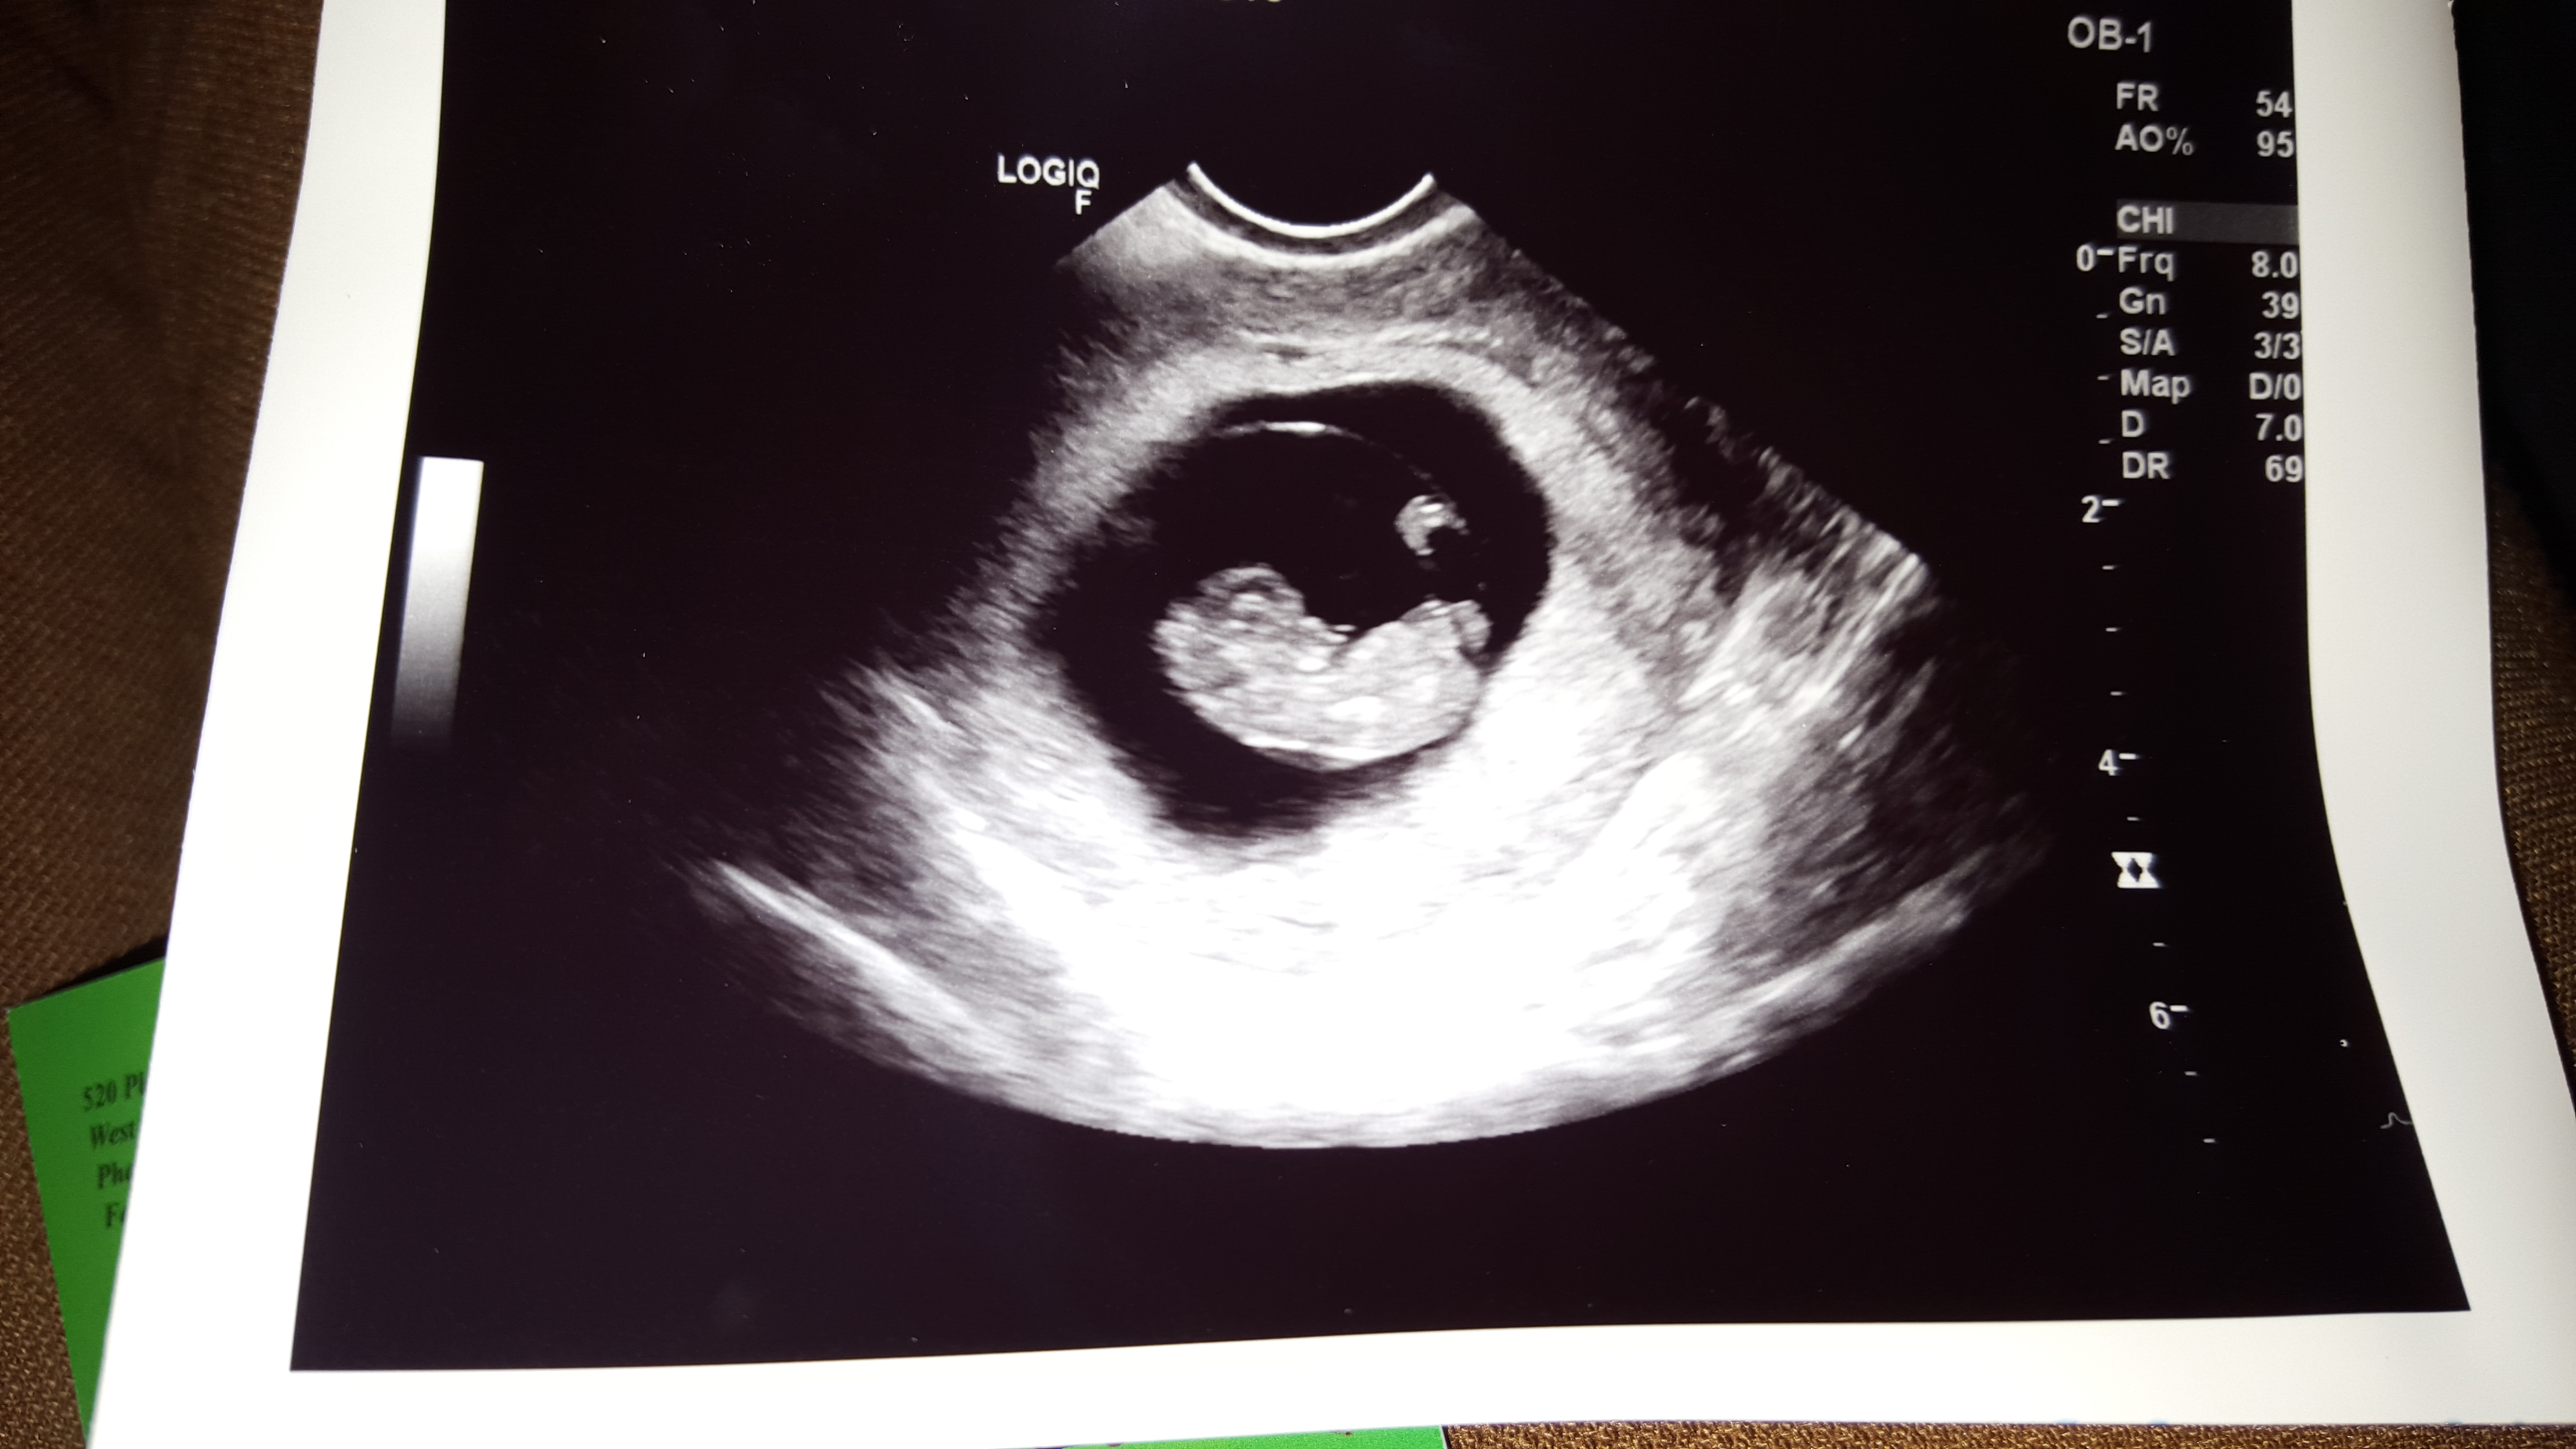

I just found out I was pregnant this week and we had our first ultrasound yesterday to find out how far along. I am 8 weeks and 3 days due June 22nd. Heart rate was 156.